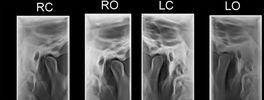

TM JOINT-X RAY